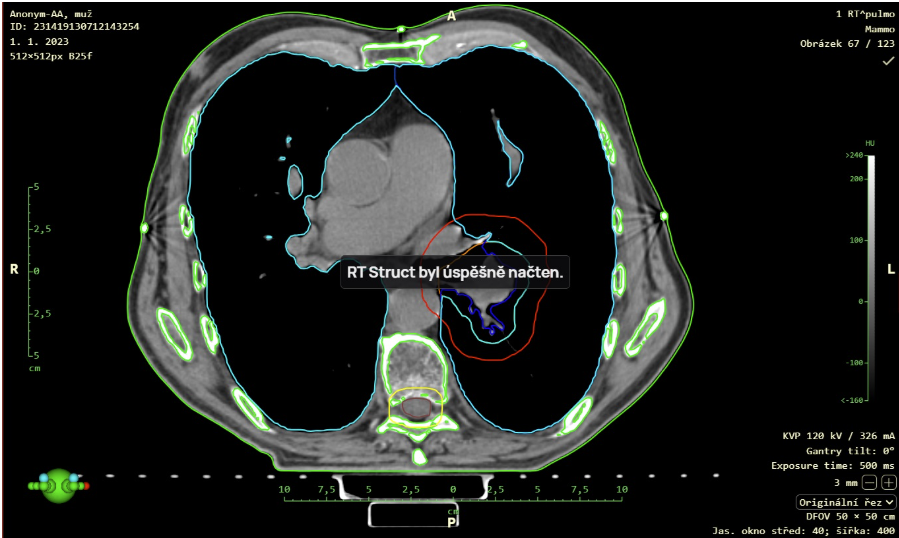

- Podpora zobrazení RTSTRUCT pomocí funkce „Načíst RT Struct“ je nyní možné zobrazit data modality RTS (Radiotherapy Structure) například vytvořený plán radioterapie nad sérií snímků modality CT. Tuto funkci vyvoláte kliknutím pravým tlačítkem myši na data RTS zobrazené v pracovní sadě snímků, čímž vyvoláte kontextové menu a následně zvolíte akci „Načíst RT Struct“.